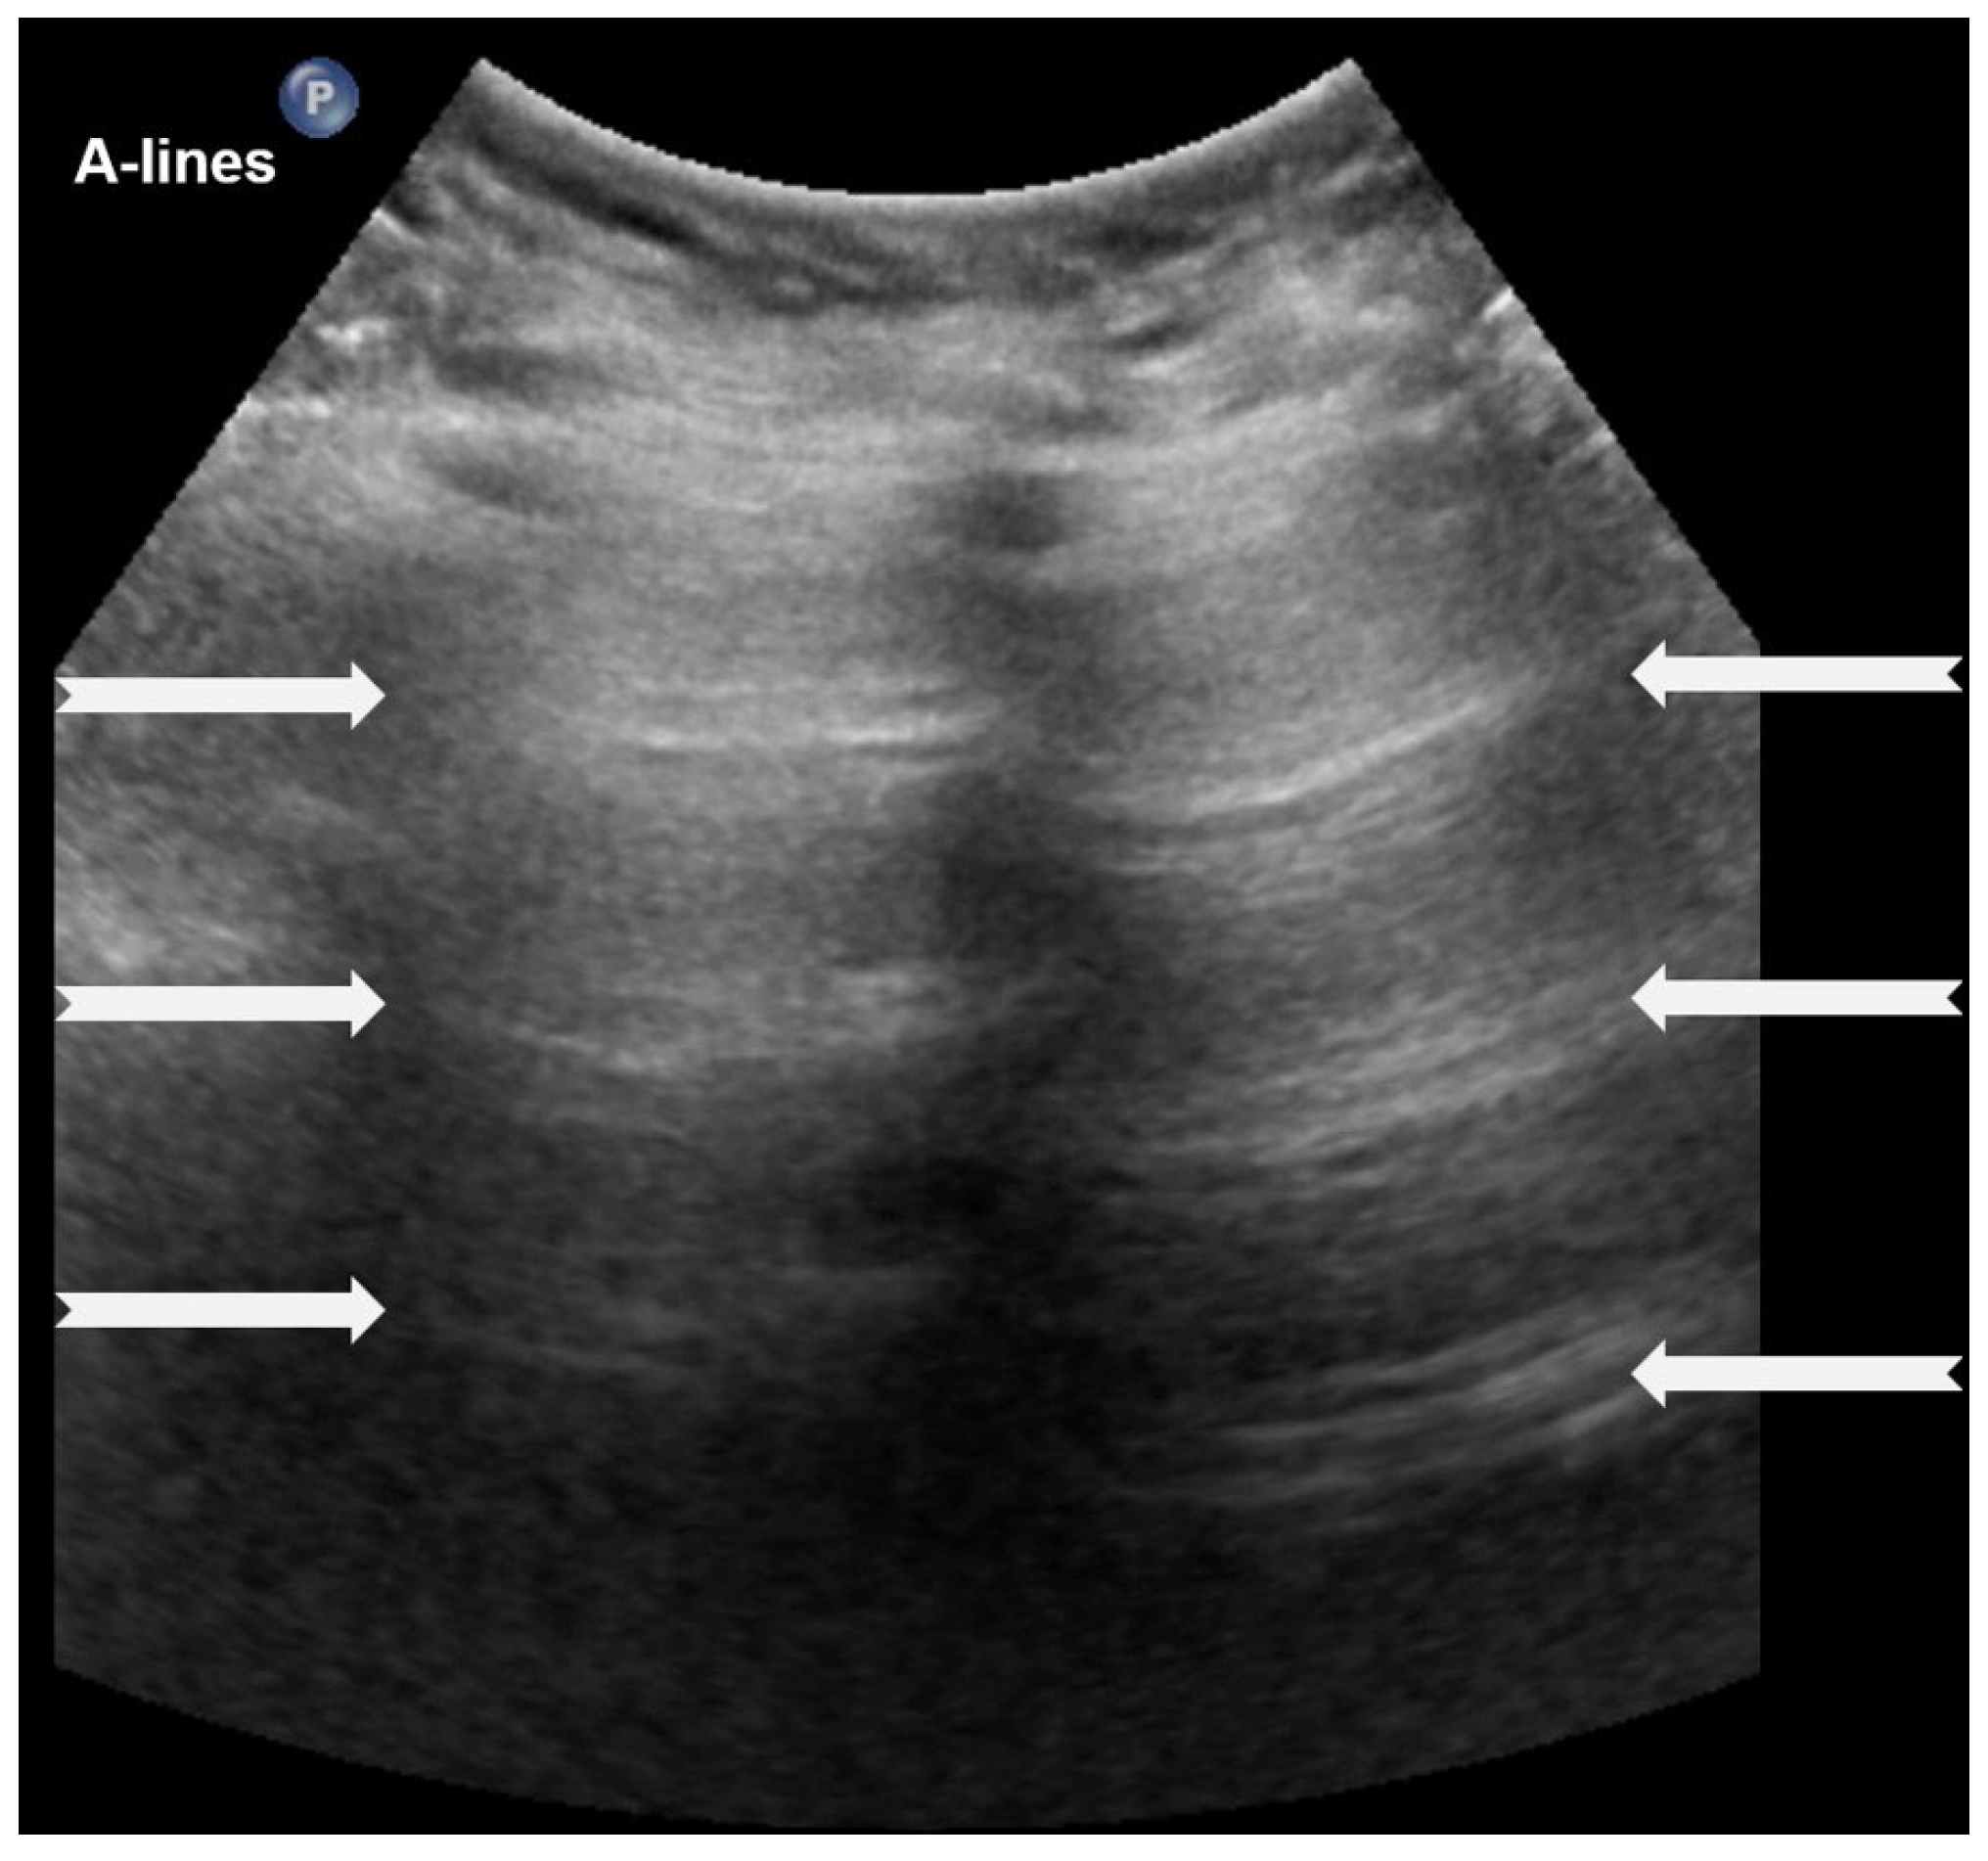

3.1.1. A-Lines